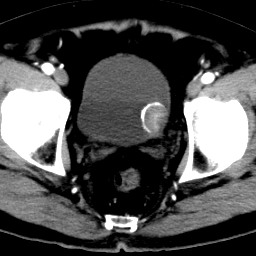

男,79岁,无痛性肉眼血尿1周。

由膀胱左侧后壁向内突出一圆形肿物,边缘光滑伴钙化,内密度均匀。支持考虑:膀胱癌!

蛋壳样钙化------应该是良性病变的影像表现。期待病理。

膀胱ca并肿瘤表面钙质沉积

膀胱左后侧壁可见软组织块影宊向腔内,边缘钙化,考虑膀胱占位,癌可能性大。

术后病理示:膀胱乳头状癌。